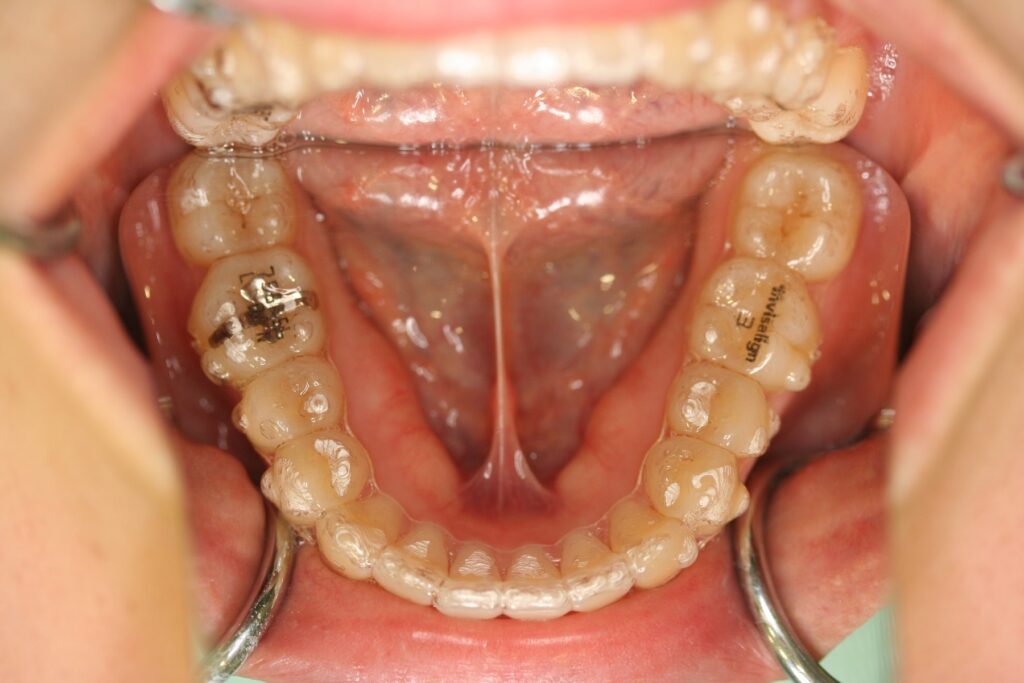

治療実績(症例) アライナー矯正 症例1 上顎前突症例 症例2 上下顎前突症例 症例3 叢生 症例4 開咬 症例5 開咬(外科的矯正治療) アライナー矯正 Post Share Hatena Line RSS feedly Pin it note 1.主訴2.診断名3.初診時年齢4.治療に用いた主な装置とオプション5.抜歯部位6.治療期間・通院回数7.総額と費用内訳総額相談検査・診断料調整料4,000円8.リスク・副作用 治療前 治療中 治療後